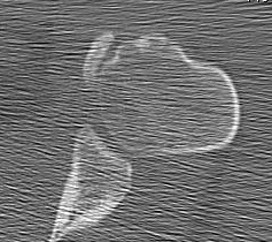

MRI

CT

Lesser tuberosity can become overgrown